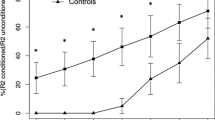

Fourteen drug-naïve PD patients and 10 patients with early CBS diagnosis were enrolled. PD patients were younger and had a lower UPDRS-ME score than CBS patients (Table 1). After a 2-year period, all PD and CBS patients met their respective diagnostic criteria, confirming clinically probable PD and possible CBS. R2BRRC of PD patients showed an increased brainstem excitability for LAS stimulation at ISIs of 100, 150 (p < 0.001) and 200 ms (p = 0.02) compared to MAS (Fig. 1A), whereas no differences between LAS and MAS were found in CBS (Fig. 1B). AI of R2BRRC at ISI of 100, 150 and 200 ms showed significant difference between groups, being higher in PD (Table 2 and Fig. 2A). Among CBS patients, only one showed atypical value (marked asymmetry) for AI of R2BRRC, while in the PD group, two patients exhibited no asymmetry of AI of R2BRRC. Multivariate analysis adjusted for age showed a significant association between diagnosis and AI of R2BRRC, with p = 0.02.

R2 Blink Reflex Recovery Cycle graph-curve for PD and CBS patients. Ratios of the conditioned R2 component (amplitude) to the unconditioned response are shown as mean + standard error (S.E.). X-axis: interstimulus intervals (ISIs) in milliseconds (ms). Y-axis: ratio of the conditioned to the unconditioned R2 response in percentage (%). A R2 Blink Reflex Recovery Cycle graph-curve of PD patients; paired t test: *p < 0.001, °p = 0.02 when comparing more affected side (MAS) stimulation vs. less affected side (LAS) stimulation. B R2 Blink Reflex Recovery Cycle graph-curve of CBS patients; no statistically significant differences were found when comparing MAS stimulation vs. LAS stimulation. PD Parkinson’s disease, CBS corticobasal syndrome

Asymmetry indexes for patients affected by Parkinson’s disease and corticobasal syndrome. Asymmetry indexes are shown as mean + standard error (bars). A AI of R2BRRC. *p < 0.001 and °p = 0.004 when comparing PD and CBS; B AI of MRI. *p = 0.01. Outliers are represented by dots. PD Parkinson’s disease, CBS corticobasal syndrome

Previous neurophysiological studies evaluated R2BRRC in PD and APs showing that PD patients exhibited increased brainstem excitability (Kimura 1973; Sciacca et al. 2020a); furthermore, an asymmetrical EMG activity with increase of blink reflex components on the LAS compared to MAS has been observed in PD patients (Dengler et al. 1982) together with the presence of a higher AI of R2BRRC differentiating PD from PSP and MSA patients (Sciacca et al. 2020a). Concerning APs, only a few studies investigated brainstem excitability by the application of blink reflex and R2BRRC (Sciacca et al. 2020a, b; Sciacca et al. 2018; Valls-Solé et al. 1997; Szmidt-Salkowska et al. 2016) showing that PSP and MSA patients exhibited an increased brainstem excitability compared to CBS patients. In this study, we added and confirmed previous data showing that PD and CBS patients at the early stages of disease presented an inverse pattern of brainstem excitability, with PD patients showing an increased excitability in LAS compared to MAS and a higher AI of R2BRRC, whereas CBS group did not show any differences between LAS and MAS excitability.